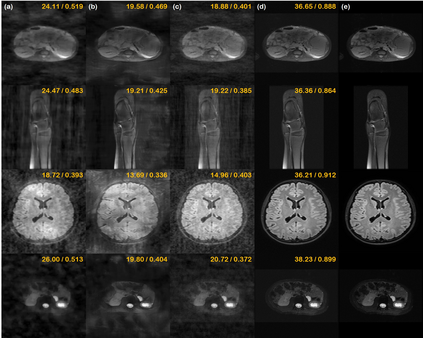

Score-based diffusion models provide a powerful way to model images using the gradient of the data distribution. Leveraging the learned score function as a prior, here we introduce a way to sample data from a conditional distribution given the measurements, such that the model can be readily used for solving inverse problems in imaging, especially for accelerated MRI. In short, we train a continuous time-dependent score function with denoising score matching. Then, at the inference stage, we iterate between numerical SDE solver and data consistency projection step to achieve reconstruction. Our model requires magnitude images only for training, and yet is able to reconstruct complex-valued data, and even extends to parallel imaging. The proposed method is agnostic to sub-sampling patterns, and can be used with any sampling schemes. Also, due to its generative nature, our approach can quantify uncertainty, which is not possible with standard regression settings. On top of all the advantages, our method also has very strong performance, even beating the models trained with full supervision. With extensive experiments, we verify the superiority of our method in terms of quality and practicality.